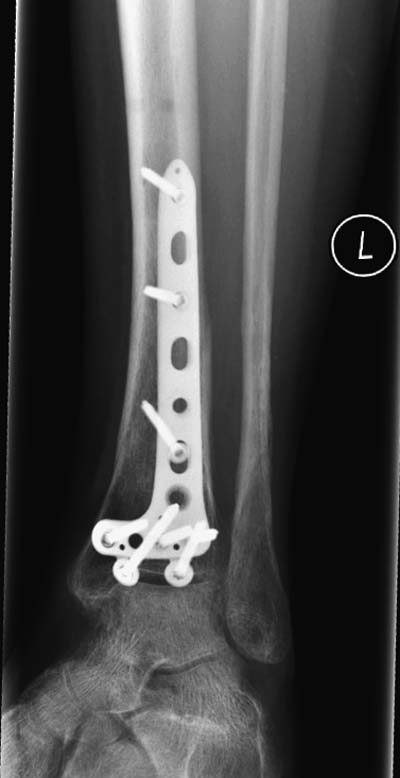

Второй случай в результате скоростной травмы, кроме пилона, вовлечение других органов! Отек при поступлении и открытый перелом на другой стороне. В таких случаях нет смысла спешить, и временный наружный фиксатор на несколько дней. После спадения отека фиксация передне-наружной пластиной. Реабилитация - ранние движения, без нагрузки.